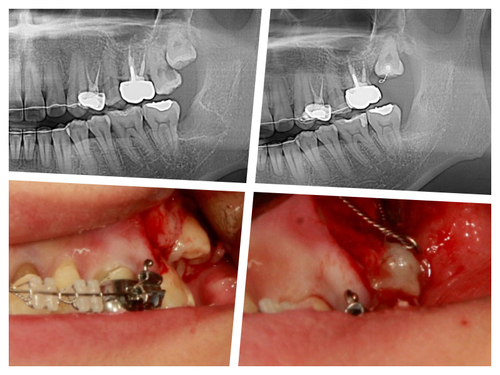

27세 여자 환자 좌측 제2대구치를 발치해야한다는 진단을 받고 상담 중 사랑니를 교정해서 위치시키고 써보자고 얘기했다~

수술을 통해 장치를 위치시키고 열심히 구강내로 당겨내고 있다.